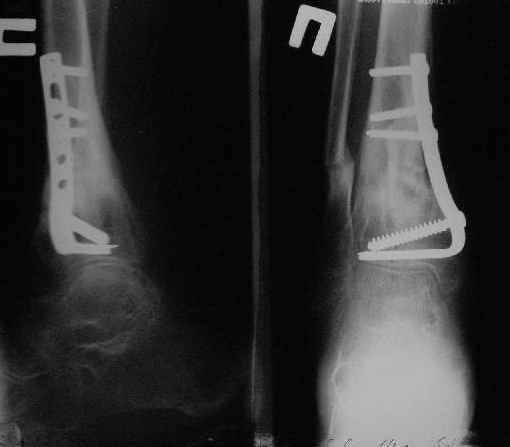

Уважаемые коллеги!Поступила пациентка 40лет, псевдоартроз Н/3 большеберцовой кости, оперирована 1,5-а года назад по поводу перелома ПИЛОНА в Австрии, травма горнолыжная.

после остеосиннтеза |  05.07.04 |  12.04.05 | Пластина удалена через 4-е месяца (миграция винтов), полимерная повязка на 2-а мес. Беспокоит деформация голени,укорочение 1-1,5см, боли незначительные, движения в г/стопном суставе в полном объёме, ходит с полной нагрузкой на ногу, подвижность в переломе не определяется. Одномоментное исправление деформации, костная пластика (chronOS)+ пластина? Аппаратная коррекция, затем пластина? Аппарат? Прошу Ваших советов. С Уважением А.Миронов